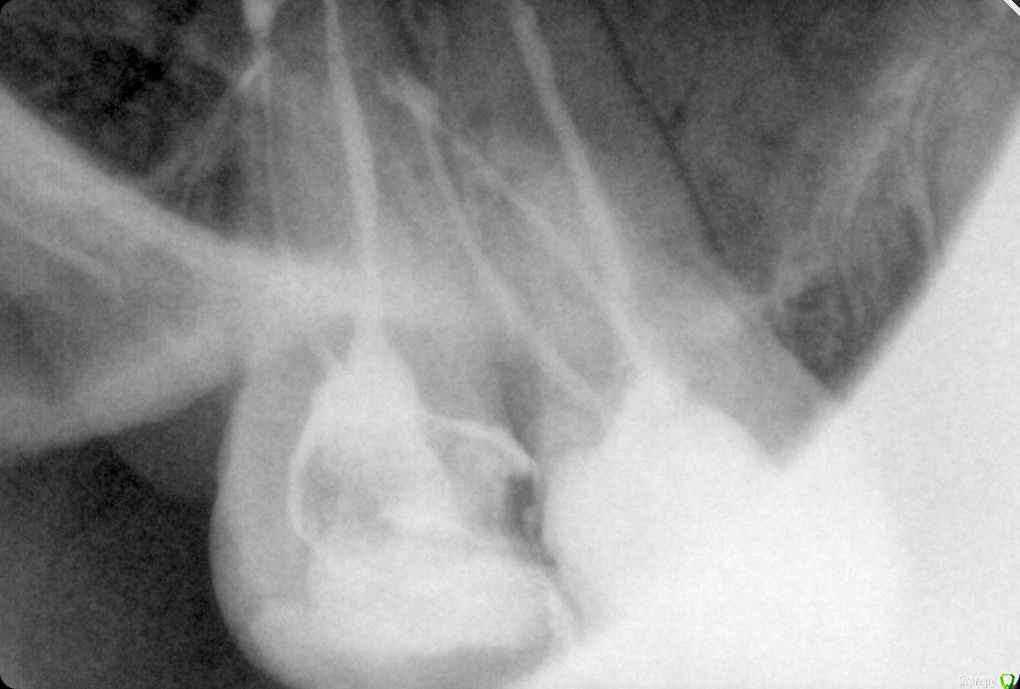

ozbourne87 Опубликовано 5 октября, 2018 Поделиться Опубликовано 5 октября, 2018 Добрый вечер! Подскажите причину боли в зубе(самый последний верхний),второй месяц лечится зуб, кальций закладывали. Пломбировали световой пломбой,потом опять болел зуб, снимали пломбу закладывали что то еще и все равно побаливает. Снимок во вложении-щас в каналах йод с каким то контрастным веществом и временной пломбой Ссылка на комментарий

shishok Опубликовано 6 октября, 2018 Поделиться Опубликовано 6 октября, 2018 А сколько каналов нашли?Мне одной кажется,что медиальный щечный канал пустой? Ссылка на комментарий

ozbourne87 Опубликовано 8 октября, 2018 Автор Поделиться Опубликовано 8 октября, 2018 Два канала нашли Ссылка на комментарий

ozbourne87 Опубликовано 8 октября, 2018 Автор Поделиться Опубликовано 8 октября, 2018 Прилагаю ещё пару снимков Ссылка на комментарий